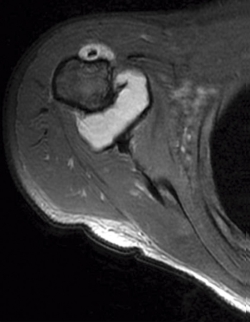

Se realizaron radiografías anteroposterior y axial de hombro, objetivándose calcificaciones intraarticulares, redondeadas, bien delimitadas. Ante dichos hallazgos, se procedió a la realización de una resonancia magnética (RM). En dicha prueba se objetivaron lesiones quísticas múltiples, bien delimitadas, algunas de ellas isointensas en T1, junto a otras lesiones hipointensas en T1 y T2 en la articulación glenohumeral compatibles con el diagnóstico de condromatosis sinovial (Figuras 1 y 2).

Figura 1. Resonancia magnética, T1 corte axial: condromatosis sinovial.

Figura 2. Resonancia magnética, T2 corte coronal: condromatosis sinovial.